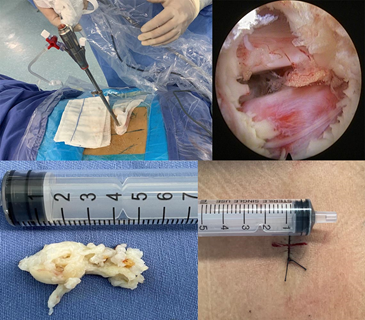

随后经扩张管道放入工作通道,然后在内镜直视下只需在黄韧带上开一个小口,即可将工作通道进一步置入椎管内;直视下辨识硬膜囊、神经根和突出的椎间盘组织,用髓核钳等工具摘除突出的椎间盘组织,手术即告完成。

通常手术切口大约在8mm,出血一般都很少,多数不到10ml;仅切除少部分黄韧带,对脊柱的稳定性和正常活动功能没有任何影响。